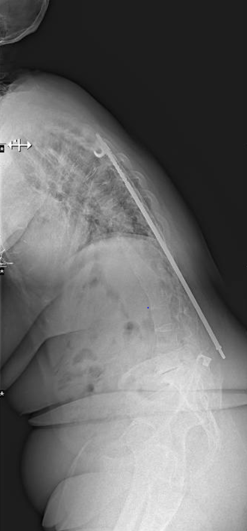

Severe malalignment case: Performed T12-S1/Pelvis posterior instrumentation, TLIF at L5-S1 & L5 PSO. No anterior approach on vascular team's advice. Patient now stands upright & grateful. #SpineSurgery #MedTwitter #scoliosis #flatback #HarringtonRods #ScoliosisWarrior

50s patient with severe malalignment. How would you treat this surgically? Nnee compensation in coronal and sagittal planes. Options: Multisegment instrumentation, TLIF/ALIF/OLIF, PSO, refer to another surgeon? Thoughts? #neurosurgery #spine #scoliosis #flatback #harringtonrods